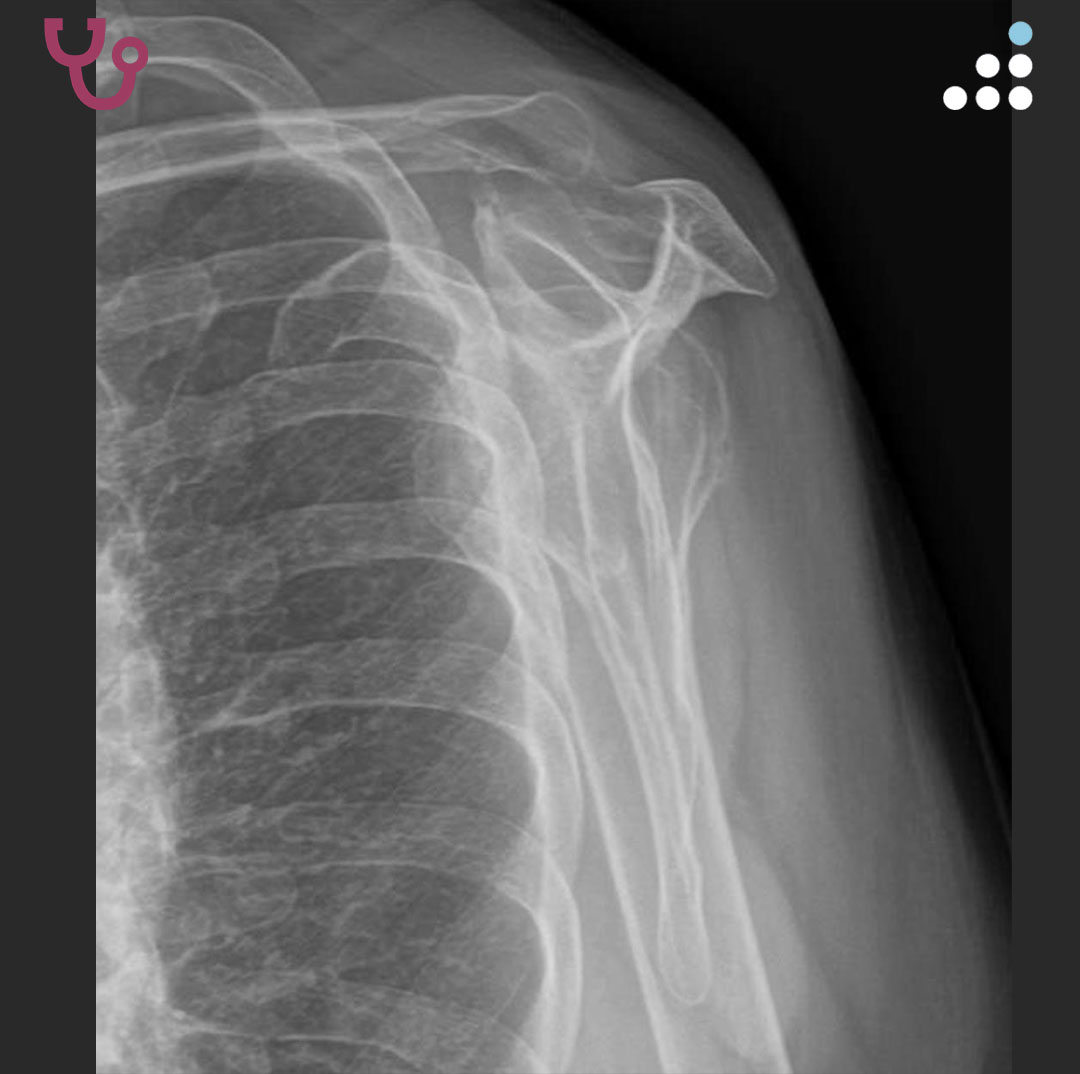

@orthobullets If there is still some cartilage left on the reverse Hill Sachs I’ve had some luck with doing a humeral head osteoplasty. I’ll use allograft chips or cement to backfill the defect after I tamp up articular surface and then try to get everything repaired especially in young pts